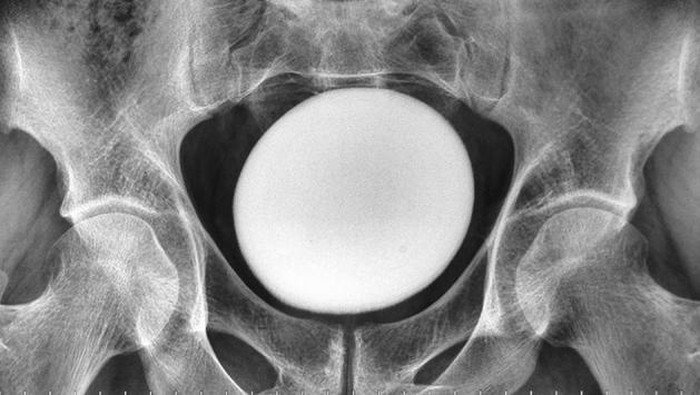

Dokter di Iran menemukan batu kandung kemih raksasa di tubuh pasien pria berusia 35 tahun. Ukurannya seperti telur burung unta, dan kasus ini jarang terjadi. Pasien mengeluhkan rasa tidak nyaman di area saluran kemih, namun tidak mengalami gangguan saat berkemih atau memiliki riwayat penyakit terkait sebelumnya.

Dokter menemukan massa besar yang halus dan keras di atas tulang kemaluan (pubis) pasien. Massa tersebut tidak melekat pada area panggul atau dinding perut. Pemeriksaan ini dilakukan di klinik urologi Imam Reza Hospital, Iran, menunjukkan bahwa kasus ini cukup langka.